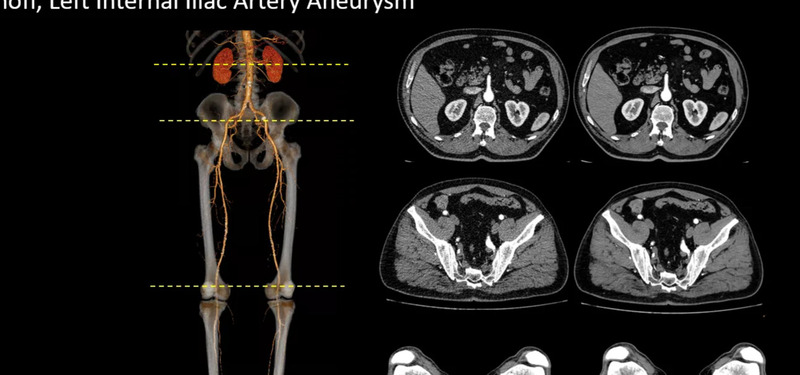

Реконструкция изображений с помощью нейронной сети глубокого обучения

Применение искусственного интеллекта при реконструкции изображений позволяет снизить лучевую нагрузку на пациента, повысить выявляемость патологий и уменьшить рабочий шум. Обработка изображений для большинства протоколов занимает менее 60 сек.